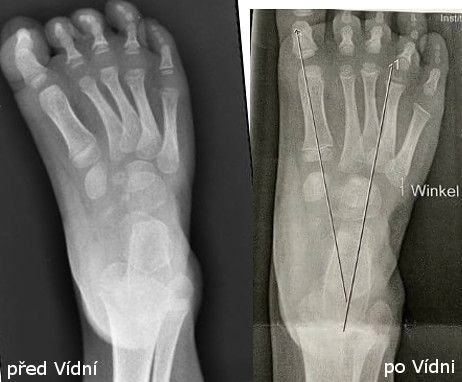

Ve Vídni působí nejbližší certifikovaný lékař Ponseti metody Dr. Christofer Radler, a to byla jejich poslední naděje. I když to znamenalo každý týden 8 hodinovou cestu a úhradu všech lékařských úkonů (neboť zde neplatí naše pojištění).

Bylo potřeba začít úplně od začátku – znovu 5 sáder (konečně správně dle Ponseti metody)  a opět udělat malý operační zákrok (tenotomie).

A tady je konec dlouhé cesty Písek – Praha – Brno – Vídeň, mnoha naježděných kilometrů a velké odvahy jít si za svým.

Dnes má malá Natálka 6 let, nejhorší období má za sebou a se správnou léčbou to zvládla i bez operací. Má velkou naději na plnohodnotný život bez omezení a bolestí.